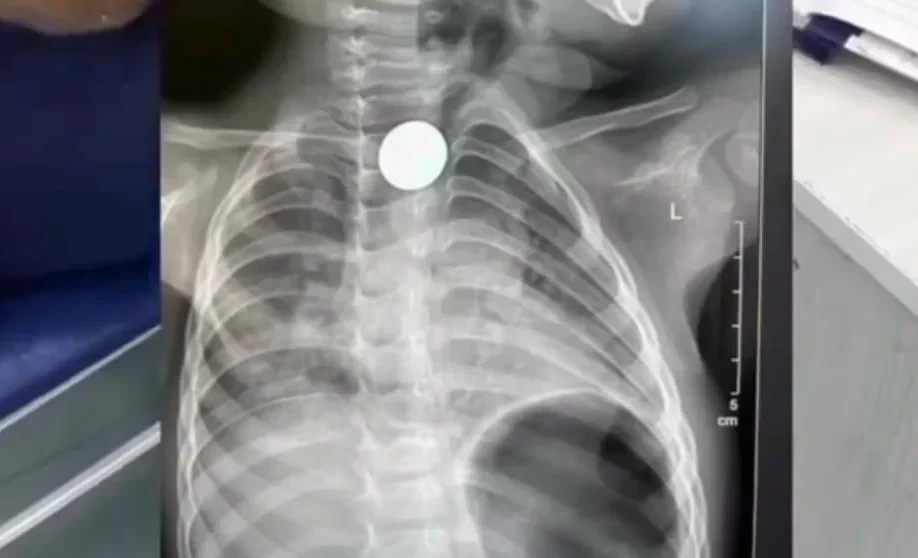

В Бишкеке врачи без операции извлекли монету из пищевода двухлетнего ребенка

В столице Кыргызстана, Бишкеке, сотрудники Городской детской клинической больницы скорой медицинской помощи №3 успешно справились с задачей извлечения монеты из пищевода двухлетнего ребенка, не прибегая к операции. Об этом стало известно из сообщения пресс-службы медицинского учреждения.

Медицинские работники сообщили, что юный пациент был доставлен в Бишкек из Нарына. Монета застряла в области второго физиологического сужения пищевода, и в трех других больницах, куда обращались его родители, врачи не смогли ее извлечь.

В столичной больнице специалисты применили малоинвазивный метод с использованием катетера Фолея, что позволило избежать разрезов и оперативного вмешательства.